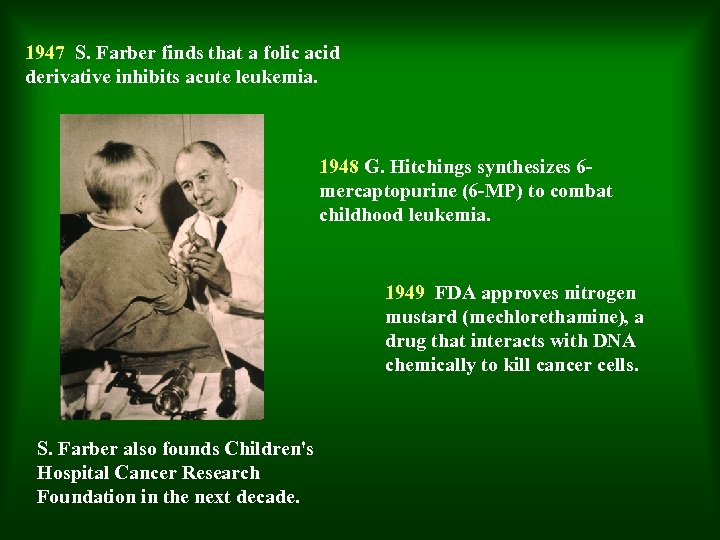

1947 S. Farber finds that a folic acid derivative inhibits acute leukemia. 1948 G. Hitchings synthesizes 6 mercaptopurine (6 -MP) to combat childhood leukemia. 1949 FDA approves nitrogen mustard (mechlorethamine), a drug that interacts with DNA chemically to kill cancer cells. S. Farber also founds Children's Hospital Cancer Research Foundation in the next decade.